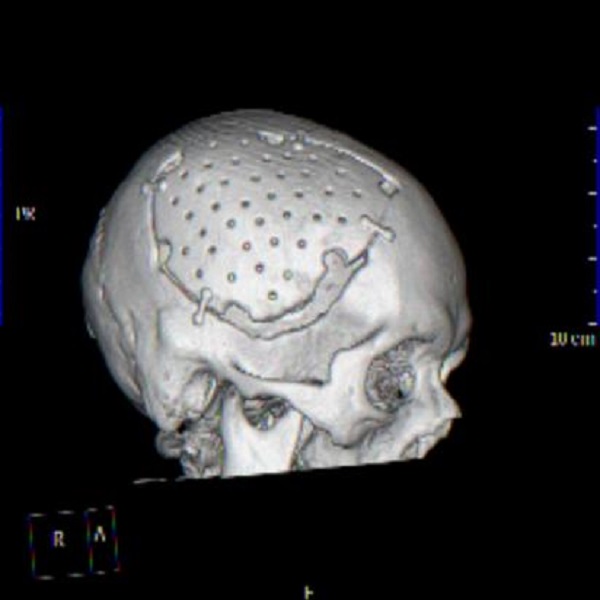

(自体颅骨修补后三维复建图,贴合人体正常生理解剖)

1.符合人体正常生理,基本不会产生排斥反应,也无需额外的材料进行塑形。

2.除保持原有的颅骨形态外,还可减少头皮反应性水肿及皮下积液,修补后外观更加接近于解剖学特点。